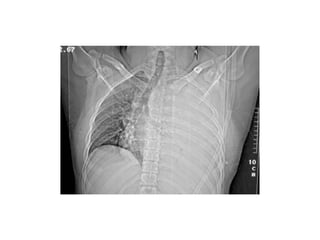

Respiração paradoxal ou

Tórax instável

• Giram em torno de 1,4% nos traumas de

tórax;

• Provocado por fratura de múltiplas

costelas;

• MECANISMO DE TRAUMA: impacto sobre o

esterno (nas colisões frontais, o esterno pára

contra a coluna da direção e a continuação do

movimento da parede torácica posterior para

frente dobra as costelas até estas fraturarem)

ou sobre a face lateral da parede torácica (na

colisão lateral, ocorre impacto na parede lateral

do tórax). Surge quando 2 ou mais costelas

adjacentes são fraturadas em pelo menos 2

lugares.

QUANDO SUSPEITAR?

•

• Presença de movimentos torácicos paradoxais à

respiração, ou seja, à inspiração o segmento instável se

retrai e, à expiração, abaula-se, ao contrário dos

movimentos normais. No início, o espasmo da

musculatura intercostal pode impedir movimentação

paradoxal significativa;

Dor torácica mais intensa do que na fratura isolada de

costela;

Dor à palpação do tórax;

Presença de crepitações ósseas à palpação; Presença de lesões ou

equimoses no local; Taquipnéia progressiva;

Impossibilidade de respirar profundamente; Hipóxia, cianose.